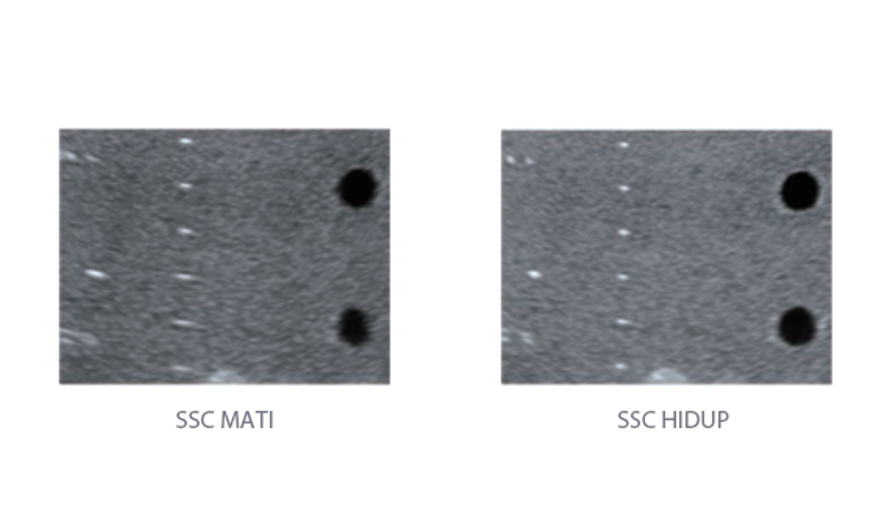

Sejak didirikan, Mindray terus mencari cara baru untuk meningkatkan keandalan diagnostik. Didukung Teknologi ZONE Sonography? terkini, platform ZST+ baru Resona 7 meningkatkan kualitas gambar ultrasound melalui pengambilan zona dan pemrosesan data saluran.